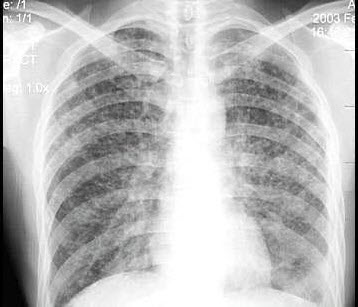

250、单项选择题

女,1岁半,发热伴咳嗽5天,如图所示,最可能的诊断为()

A.支气管炎

B.肺门结核

C.支气管肺炎

D.肺隔离症

E.以上均不正确